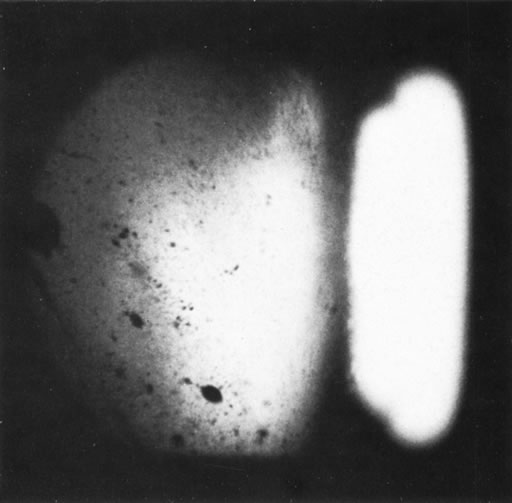

Unfortunately, imaging studies are not always diagnostic. The A- and B-scans shown in Figures 3 and 4 were from a patient with unilateral media opacity referred for evaluation and treatment of a presumed uveal melanoma. Occasionally, if the cataractous lens is scanned tangentially, artifact can occur. A repeat ultrasound at our institution was negative for tumor, and the referral ophthalmologist who performed a cataract extraction noted that no tumor was present and that the patient has an excellent visual outcome. In contrast, the patient shown in Figure 5 was referred with a presumed uveal melanoma with secondary inflammation and a history similar to that described for the patient shown in Figure 111 Ultrasound and CT examinations were not diagnostic. Because the eye was blind and painful, it was enucleated, and an extremely necrotic uveal melanoma was noted histologically. In some necrotic melanomas, the fundus cannot be visualized and the diagnosis cannot be established with imaging studies. Very rarely, a necrotic uveal melanoma can produce sufficient pigment dispersion into the vitreous to obscure the correct diagnosis.12